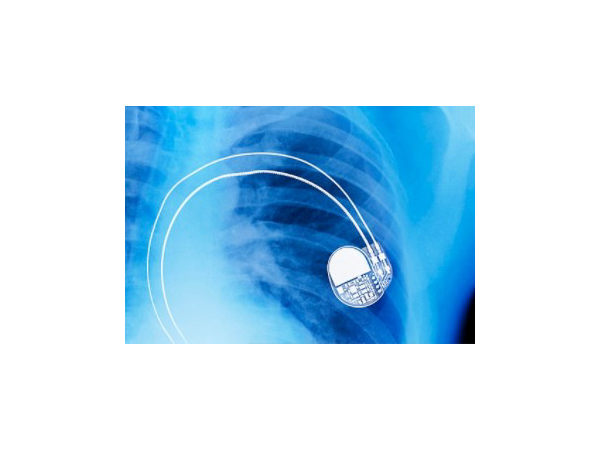

走路速度加快就暈倒,武漢4歲女童本應好動的年紀心臟竟埋起搏器!

本應是愛玩好動的年紀,卻不敢隨意跑跳,只能當一名“文靜”的乖寶寶。4歲女童因患有完全性房室傳導阻滯,劇烈活動常常會引起心臟“停跳”導致大腦供血不足,發生暈厥。3月6日,武漢兒童醫院心血管內科成功為她實施了永久起搏器植入術。